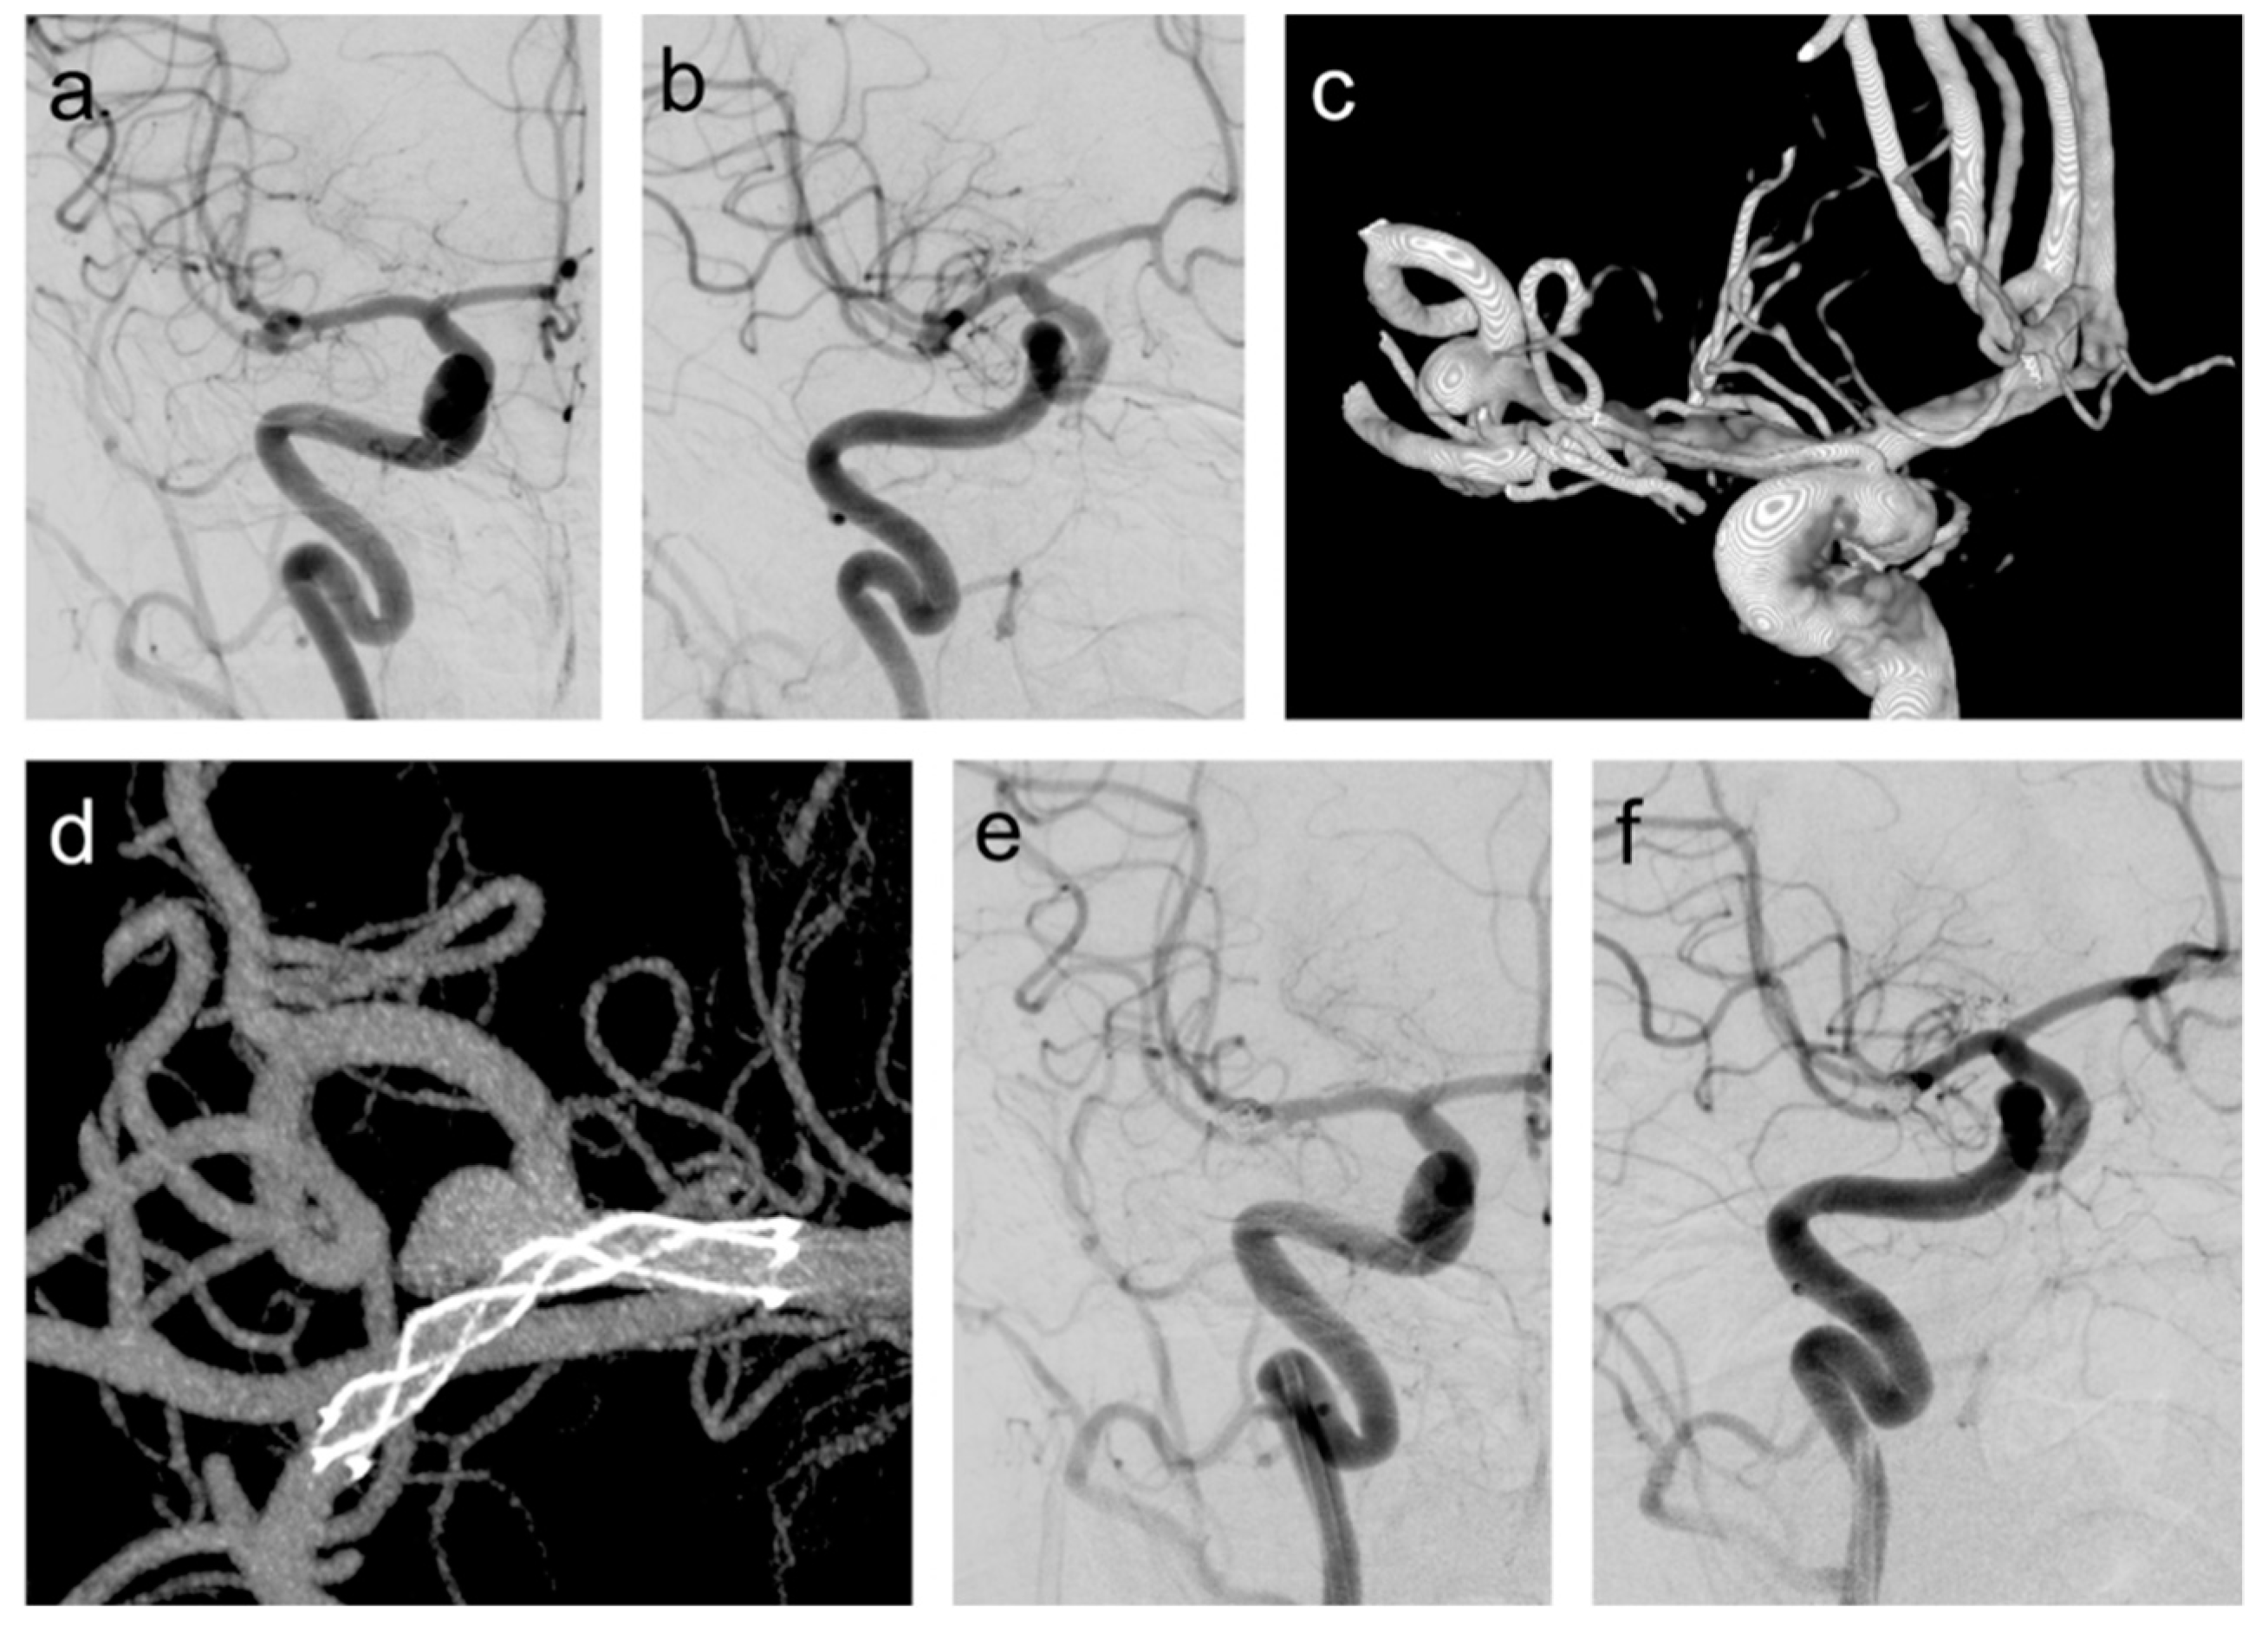

Figure 1 from Double StentAssisted (Y and X) Coil Embolization of Unruptured Intracranial Coil Embolization Of Unruptured Intracranial Aneurysms Endovascular coil embolisation continues to evolve and remains a valid modality in managing ruptured and unruptured cerebral. Between january 2012 and december 2023, 435 patients with intracranial aneurysms (316 unruptured and 119 ruptured) underwent coil embolization at our hospital. Endovascular coil embolization is an option for treatment of ruptured and unruptured intracranial. With its appeal as a minimally invasive technique,. Coil Embolization Of Unruptured Intracranial Aneurysms.

From www.researchgate.net

(PDF) Double StentAssisted (Y and X) Coil Embolization of Unruptured Intracranial Saccular Coil Embolization Of Unruptured Intracranial Aneurysms Intraprocedural aneurysmal rupture is a feared complication of coil embolization of intracranial. Endovascular coil embolisation continues to evolve and remains a valid modality in managing ruptured and unruptured cerebral. With its appeal as a minimally invasive technique, an increasing number of centers are treating unruptured and ruptured aneurysms with endovascular coil embolization. Endovascular coil embolization is an option for treatment. Coil Embolization Of Unruptured Intracranial Aneurysms.